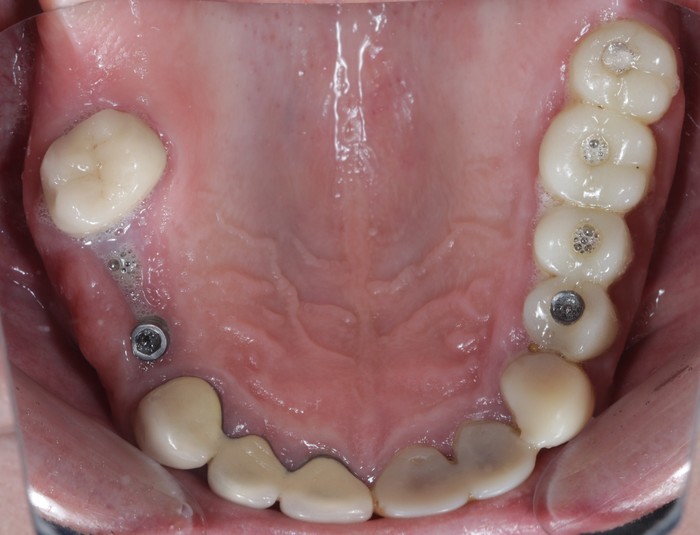

Вот пример того, когда пациент пренебрёг данным правилом:

Мужчине были установлены и спротезированы (временными коронками) имплантаты в другой клинике. После этого он пропал на несколько лет, не закончив полностью свое лечение. Явился лишь тогда, когда почувствовал «дискомфорт».

Кроме несостоятельности старых коронок и пломб, патологической стираемости зубов и т.д. - все эти годы сильно страдала гигиена.

Ниже, на панорамном снимке зубов, мы наблюдаем критичную убыль костной ткани вокруг имплантатов на верхней челюсти.